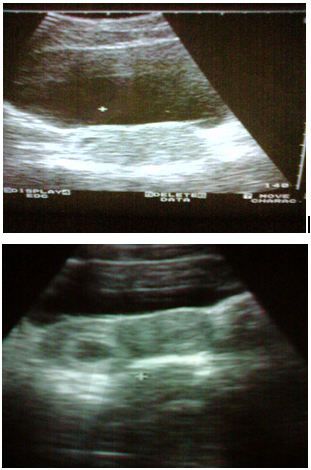

(Figures 1-3)

Figure 2 Patient Dj.B.1983 age. Ultrasound examination carried out 5 times. Spontaneously delivered a live male child 2600/50.

Figure 3 Patient G.J. 1988 age Ultrasound examination carried out 6 times. Spontaneously delivered a live male child 2600/50.